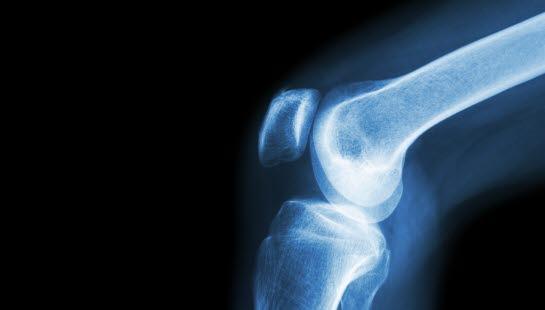

Kalsiumpyrofosfat-avleiringer er en vanlig tilstand hos eldre der kalsiumpyrofosfat-krystaller avleires i ledd eller leddnære strukturer. Krystallene avleires først og fremst i bruskstrukturer rundt og i ledd. Tilstanden kalles da kondrokalsinose. Årsaken til krystallavleiringene er ukjent, men disponerende faktorer er arv, tidligere leddskade samt enkelte sykdommer. Krystallavleiringer kan ses på et røntgenbilde uten at personen har symptomer. Kondrokalsinose kan forårsake utfelling av krystaller i leddvæsken og gi smertefulle leddbetennelser som likner på urinsyregikt (tidligere kalt "pseudogout" på engelsk). Diagnosen stilles ved påvisning av slike krystaller i leddvæsken og behandlingen er da smertestillende og betennelsesdempende medisin eller en injeksjon av kortison i leddet. Det finnes også forebyggende behandling. De fleste med kalsiumpyrofosfatavleiringer forblir uten symptomer.

Pyrofosfat-avleiringer rundt ledd kan vises på røntgen eller ultralyd og være uten symptomer. Ved leddbetennelse vil senkningen være forhøyet. Å stille diagnosen krystallartritt krever sikker påvisning av kalsiumpyrofosfat-krystallene i leddvæsken, noe som innebærer at leddvæske trekkes ut med sprøyte fra et ledd og mikroskoperes. Akutt leddbetennelse i skulder eller albue og debut i høy alder kan gi mistanke om denne typen betennelse.